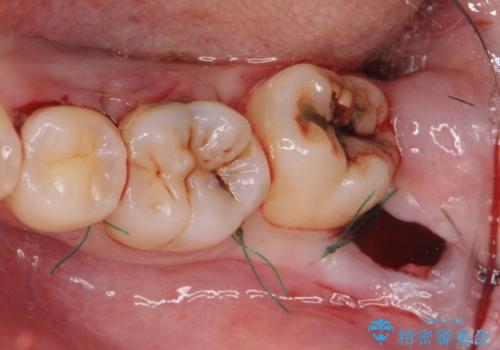

歯冠長延長術をおこなったアプローチの難しい虫歯治療

- 親知らずの抜歯を希望され来院されましたが手前の大臼歯2本に虫歯が認められ、治療が必要な状態でした。

クラウン形態にするには歯の高さが足りず設計できないため、親知らずの抜歯と共に歯周外科を同時に行うことで安定した歯周組織を獲得しセラミック治療を行う治療計画としました。

歯冠長の延長を行ったことで、安定したクラウン治療を行うことができました。